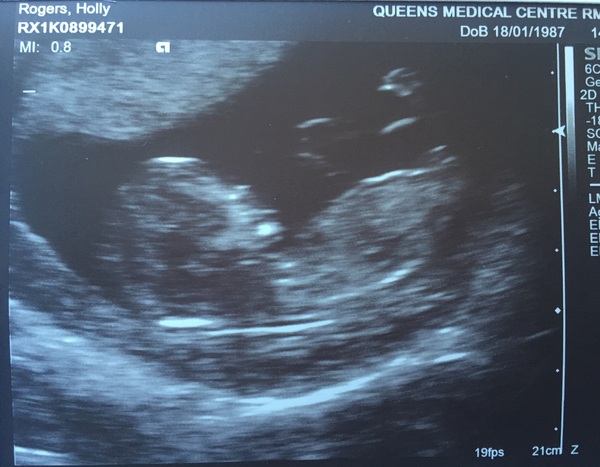

Holly1987 · 12/08/2016 20:58

Hey everyone

So the scan went really well. Before I could even begin looking for the heartbeat all o could see was my little pudding bouncing away Smile What a surreal feeling!

The measurements have now made me 12+6 rather than 13+1, so my new due date is the 18th Feb x